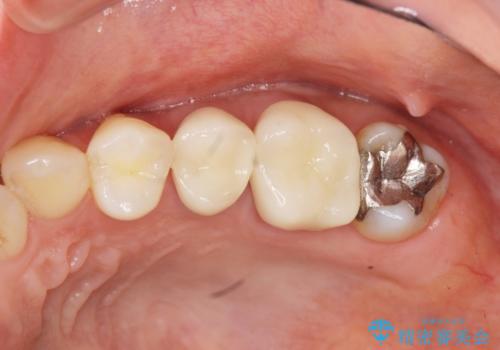

[ジルコニアクラウン治療] 笑った時に目立つ銀歯を白くしたい

![[ジルコニアクラウン治療] 笑った時に目立つ銀歯を白くしたいの症例 治療前](https://seimitsushinbi.jp/wp/wp-content/uploads/2020/07/57f6b685ec53969d2016f9c5df62fb1b-500x350.jpg?v=1595071328)